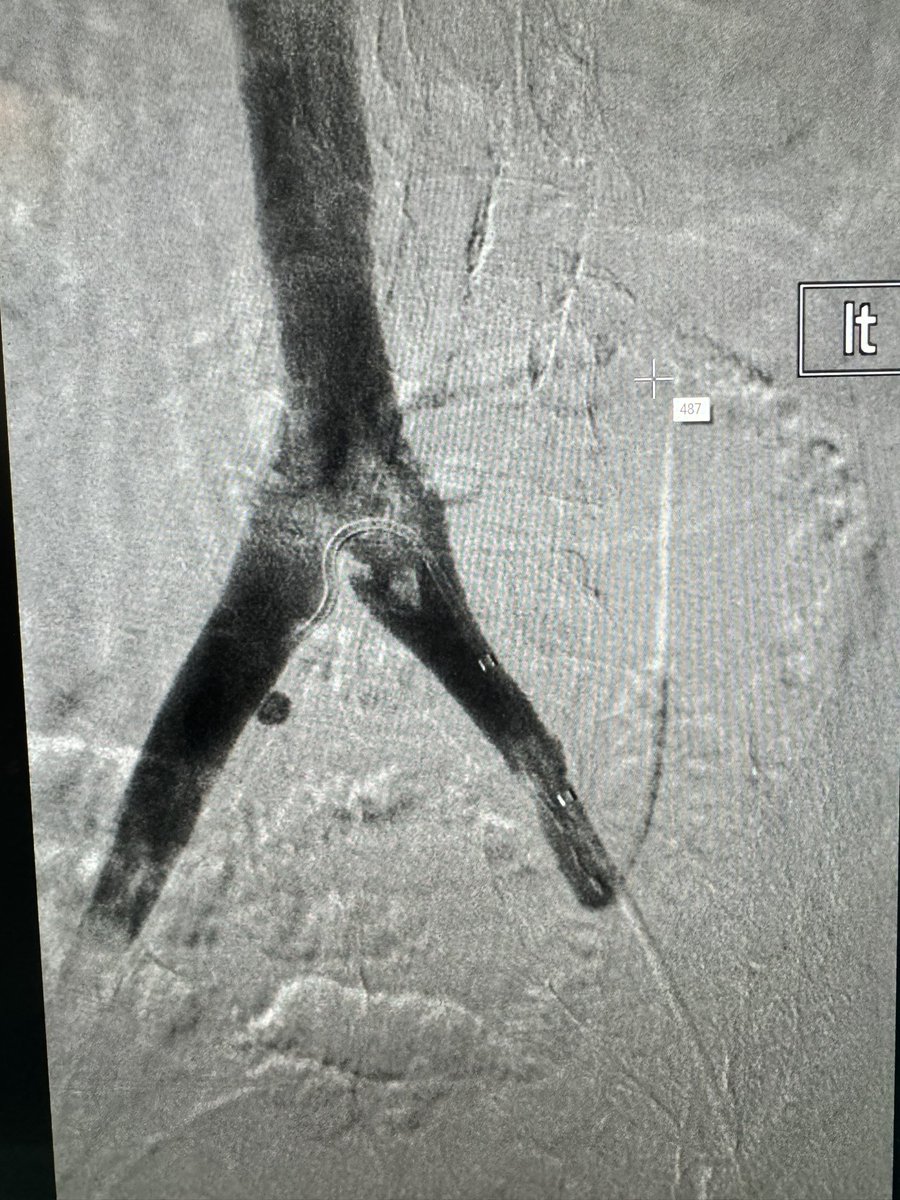

Acute, occlusive #DVT cleaned out with #ClotTriever. There was a compression defect at the iliac origin. Brought her back a few days later with #IVUS, confirmed the compression, and stented with #Abre. It felt weird to put a 12mm in the iliac, but she was petite! #IRAD

Rex Ray tweet media